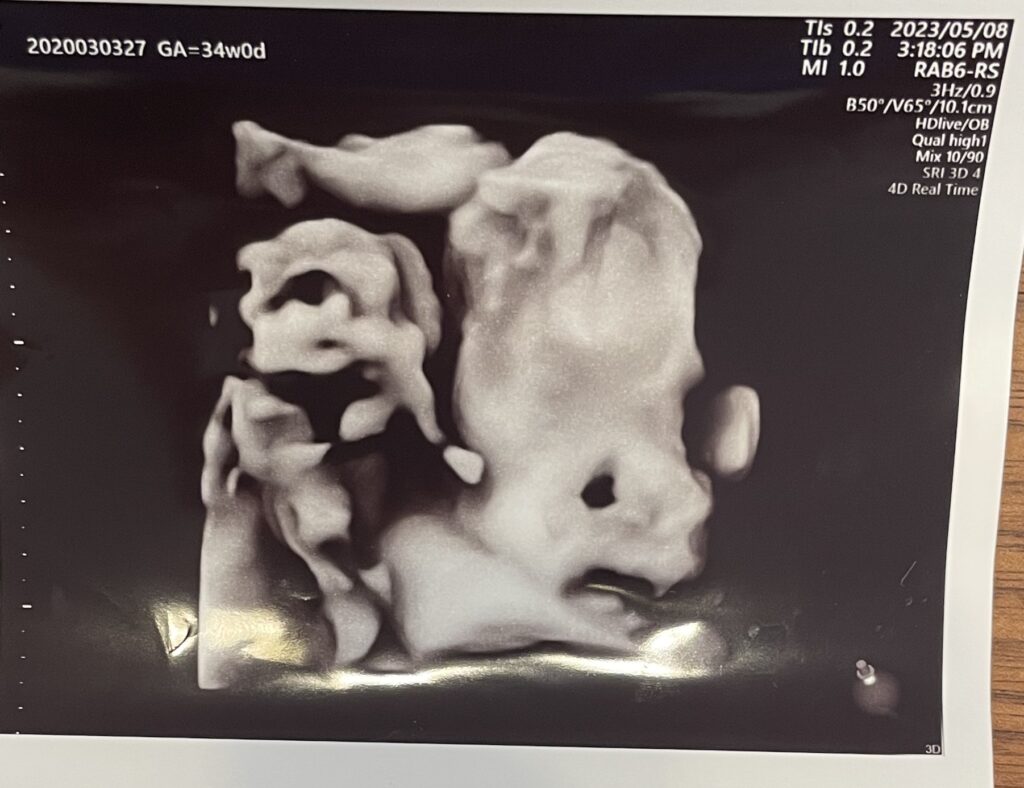

4Dのエコーの最中にお腹の中で赤ちゃんがすごく動いていて、映像が乱れていたのが怖かったです^^;

一応解説すると、向かって右側を向いていて、飛び出た丸いものが目です。笑

これを印刷してくれる先生のユーモア?は、なかなか気に入っています。